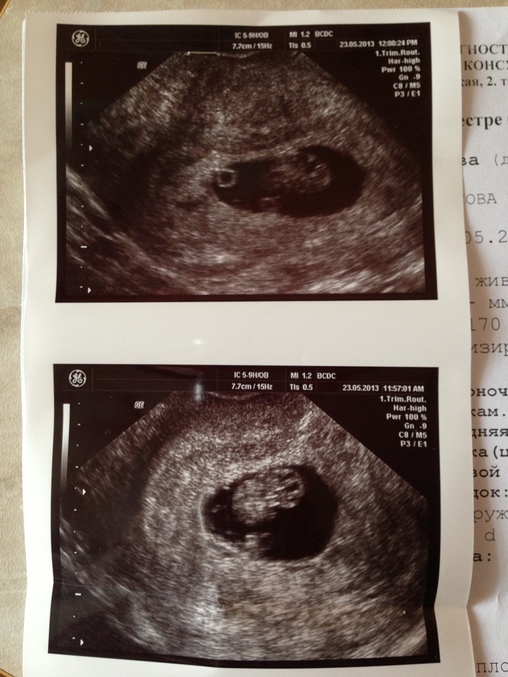

Только 23.05.13 была на первом узи т.к не по сроку заметила увеличение живота, появился за 3 дня))

Мне сразу определили двойню, чему я бузумно рада, я мечатала двойней с самого детства, хотя у меня уже есть двое деток и мне 24 года меня это не пугает а только радует.....НО...вот после узи 2 день в голову лезут всякие мысли, ни спать ни есть не могу из за этого, очень переживаю..... Мне узистка сказала что идин плод КТР 20,8мм соответствует 8 неделям а второго плода КтР 3,3мм что соотв. 6 неделям.....ВОт я себе из за этого места не нахожу, так хочется чтоб 2 выжили....Врач узист напугала что второй может замереть... Сердцебиение нормальное, чувствую себя отлично, токсикоза нет.....

Последняя дата месячных 23 сарта 2013 года....